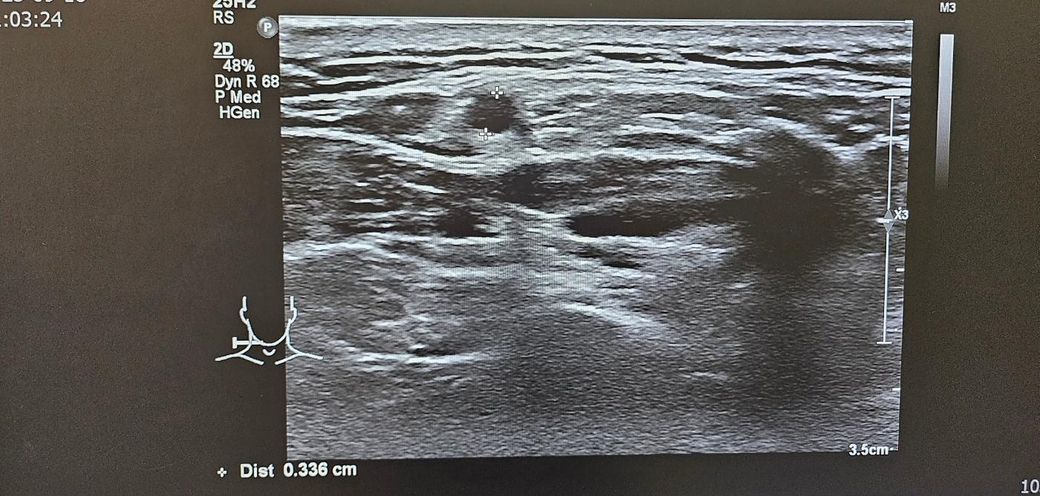

경부초음파 자세하게 설명좀 부탁드립니다

통증이있어서 초음파했는데

약먹고 통증은 없습니다

초음파 보시고 자세히 설명좀 부탁드립니다..

• 4번 째 사진